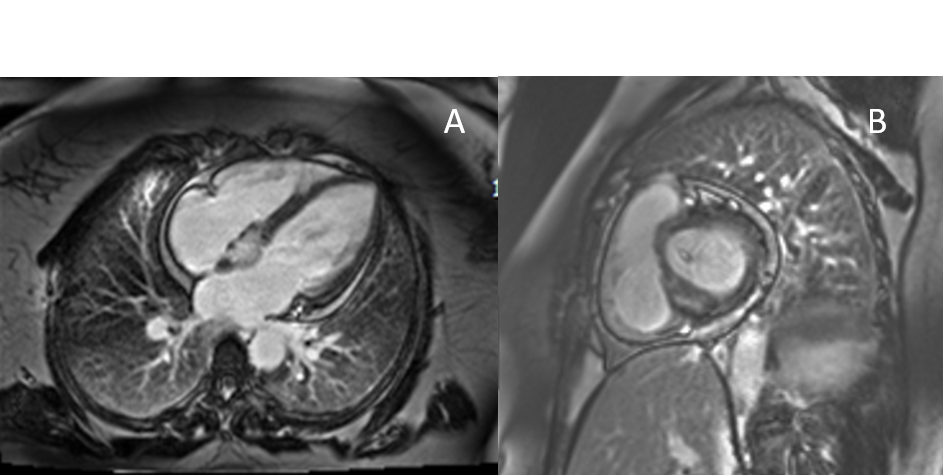

Figure 2: Short Axis T1-weighted (A) and Short Axis T2 Fat Saturation (B)